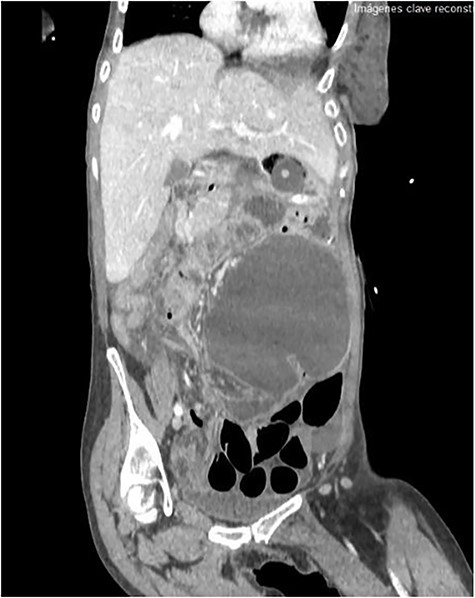

The emergency blood test showed a normochromic and normocytic anemia with an hemoglobin of 10.1 mg/dl and a leukocytosis of 11.150/ul with 70% neutrophils. The abdominal radiography showed a prominent dilation of a small bowel loop. The CT scan reported an 18-cm dilated loop. The main diagnostic suspicion was a small bowel volvulus without signs of ischemia or perforation (Figs 1–3).

However, abdominal radiographs and soluble contrasts have been relegated in favor of computed tomography. This image has a sensitivity close to 100% and a specificity of 90%. Furthermore, it allows the observation of indirect signs of complications such as necrosis or perforation [3].

Cecum volvulus is a rare pathology, so it can be difficult to diagnose. Clinically, it does not differ from other intestinal obstruction. CT scan is key to determine the etiology of the occlusive condition, as well as to show ischemia and perforation. Definitive treatment is always surgical, using one technique or another depending on the findings.